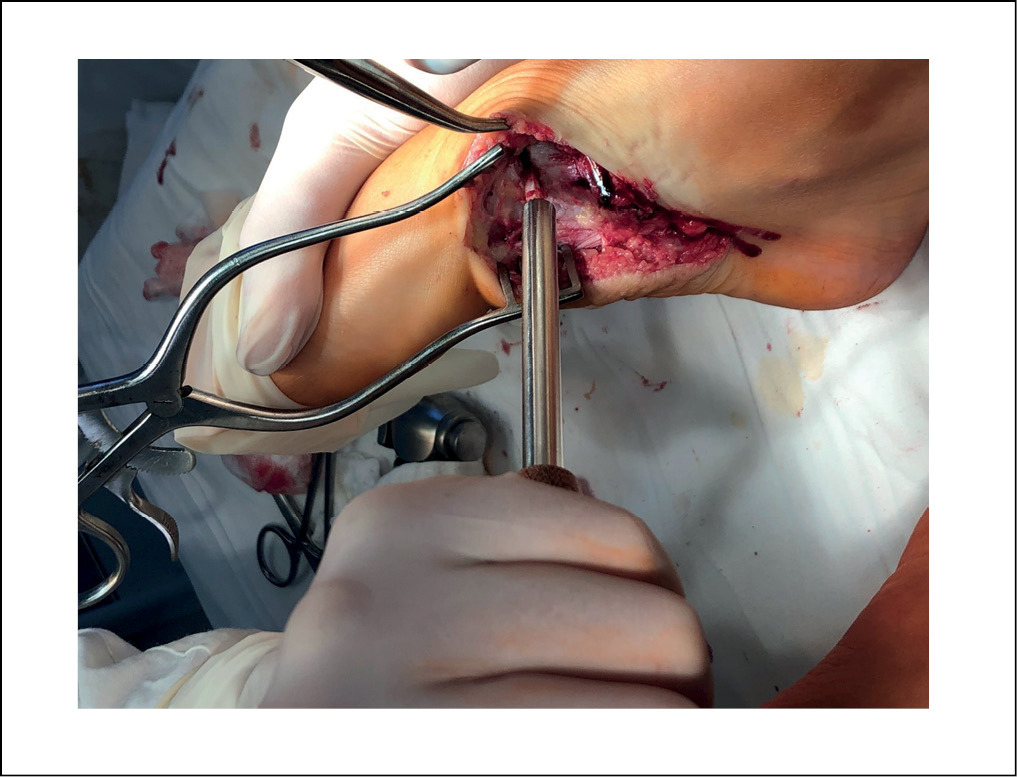

Следующим этапом производили линейный разрез до 5 см в нижней трети голени в проекции малоберцовой кости. Поднадкостнично, с минимальной травматизацией мягких тканей выполняли забор части малоберцовой кости (одного кортикала) и подготавливали его для дальнейшей имплантации и импакции в зону остеотомии медиальной клиновидной кости (рисунок 4).

Рисунок 4. Забор трансплантата из малоберцовой кости. / Figure 4. Fibular graft harvesting.

При помощи пилы выполняли клиновидную расклинивающую низводящую остеотомию медиальной клиновидной кости с установкой ранее подготовленного аутотрансплантата, тем самым опуская 1 луч стопы и устраняя излишнюю пронацию, исправляя деформацию переднего отдела (рисунок 5).

Рисунок 5. Импакция трансплантата в зону остеотомии медиальной клиновидной кости. / Figure 5. Impression of the graft into the zone of osteotomy of the medial sphenoid bone.